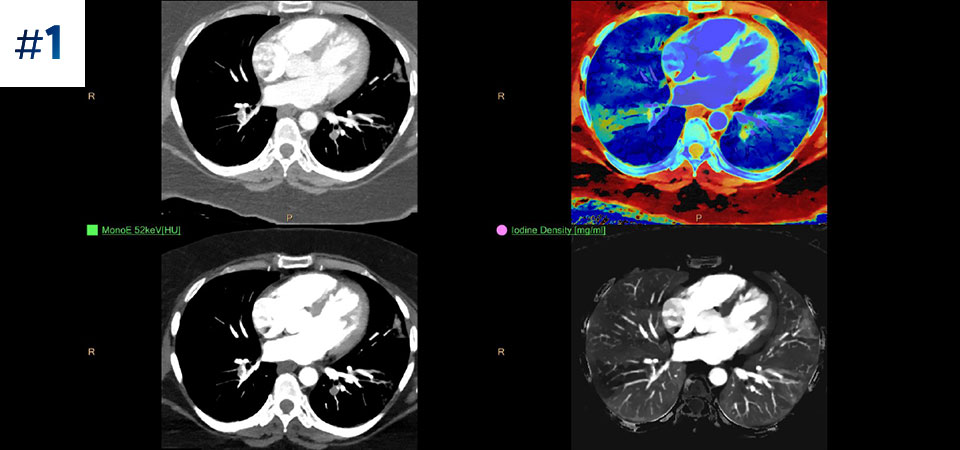

Scan as usual A single scan for fast, low-dose conventional and spectral data for every patient, every time.

Always available 100% spectral, 100% of the time for results that are always available on-demand, even retrospectively.

Reduced follow-up exams Improved tissue characterization and visualization may reduce the need for follow-up scanning for sub-optimal exams and incidental findings.

Go beyond conventional CT. See how layers of spectral-detector results can enhance your diagnostic confidence.

See the difference between spectral-detector CT and conventional CT